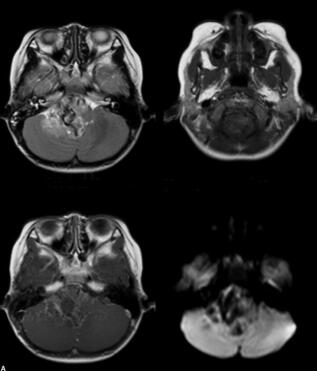

男,5岁,一天前无明显诱因出现头痛,为额部持续胀痛,当时未予特殊治疗。今日仍有头痛症状,进食后呕吐,精神状态差(图1)。

图1 右侧桥小脑区可见类圆形肿块影,以稍长T1稍长T2信号为主,中心可见条状短T1信号影。病灶边界不清,形态不整,第四脑室明显变窄。病变向上生长达脑干,向下生长达延髓。增强扫描病变明显不均匀强化。右侧听神经显示欠佳。幕上脑室普遍增宽,中线结构居中